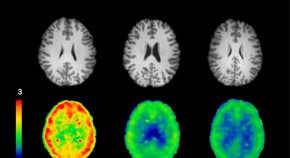

Lasting complete remission from widespread bone metastases is rare. The case of a 41-year-old premenopausal woman diagnosed with right-sided infiltrating ductal breast carcinoma andBRCA2mutation is described. She received high-dose anthracycline-based induction chemotherapy followed by autologous bone marrow transplantation with high-dose alkylator and platin-based conditioning regimens. The authors comment on the reasons for this unusual and sustained complete remission from widely metastatic breast cancer and the patient-specific factors that may have contributed to this outcome.